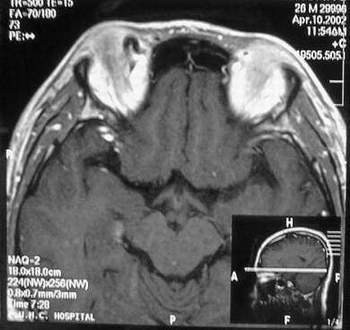

MRI及增强结果如下:

患者压颈及其它Valsava试验结果阴性。从MRI分析,在T1、T2、T+C检查该支血管均为明显流空现象,说明该血管血流速度很快,而从走行和分布看,眼上静脉可能性很大。也许也不能除外异常的眼动脉或异常血管。眶内主要可能的血管病变包括颈内动脉海绵窦瘘(高流窦)、AVM、眼眶静脉曲张、海绵状血管瘤、静脉性血管瘤、毛细血管瘤和眶内动脉瘤。。 1、颈内动脉海绵窦瘘:该患者临床有一部分支持该诊断。但从影像分析,海绵窦未见明显扩张;眼外肌未见明显充血扩张的长T1、长T2信号;颈内动脉海绵窦瘘常可见继发到血栓,可见到短T1、长T2的血栓信号。 2、眼眶静脉曲张:该疾患一般常见于小儿。该患大多数会出现Valsava试验阳性,间歇性突眼。不符合该患。影像学检查,于曲张静脉内常可见血栓和静脉石。所以不符合该患。 3、AVM:患者目前的影像学资料尚不全面,但可符合该诊断。临床上改病常见于30岁左右年轻人,单侧发病,于本患较符合。问题在于临床没有明确的血管杂音,似乎难以解释。 4、该患影像学与海绵状血管瘤差别很大,所以可基本排除此诊断。 5、静脉性血管瘤和毛细血管瘤:MRI中等T1、长T2信号,较易与本病鉴别。 6、眶内动脉瘤:我觉得患者并不能排除本病,但同样,由于波动性阴性,似乎也难以解释。 纵上所述:本人觉得,患者AVM可能性较大,同时不能除外眶内动脉瘤。 关于进一步检查,我觉得DSA价格过于昂贵。是否可先进行彩色多普勒检查,首先可以明确是静脉系统还是动静脉瘘抑或是动脉瘤。第二步,可进行MRA检查,可以清楚地显示海绵窦地相关关系,并可借此诊断或排除颈内动脉海绵窦瘘。如还需第三部检查,可进行MRV检查,对静脉系统进一步评价。三种检查总共的费用2000多圆,但给予我们的信息量已经很丰富了。 敬请各位医师提出自己的见解。 谢谢!